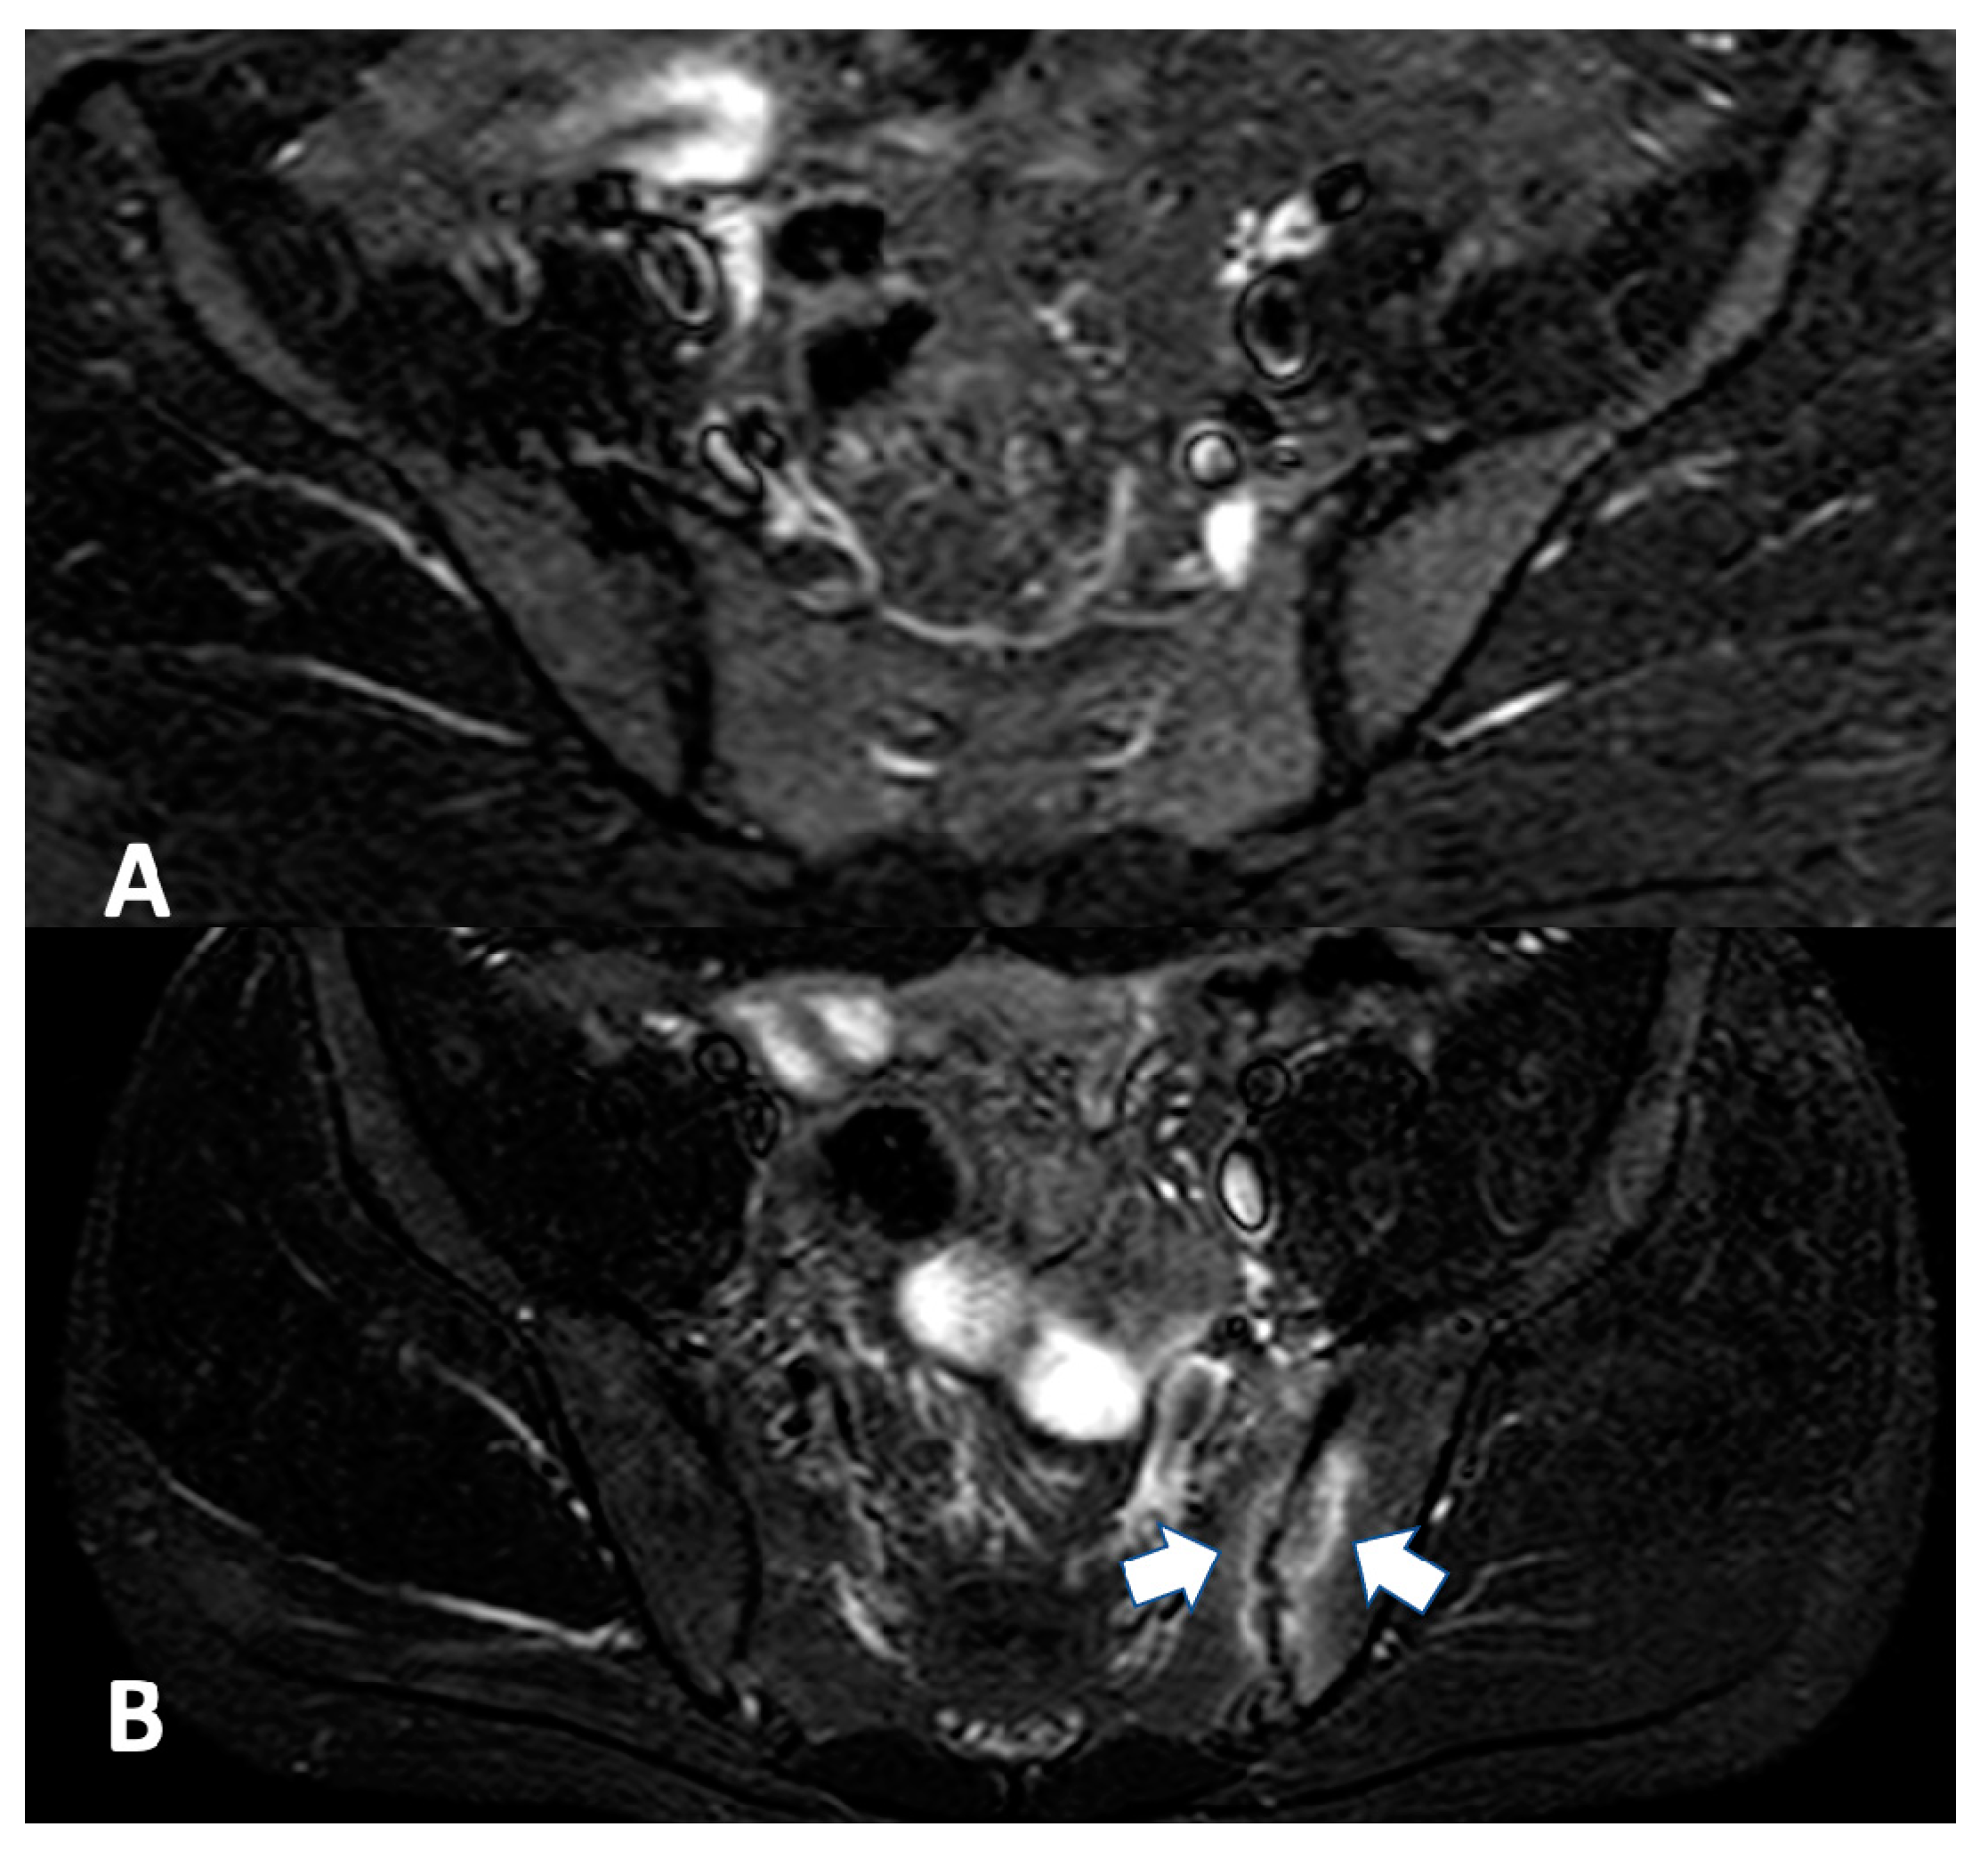

2.2.1. Sacroiliac Joint

2.2.2. Spine